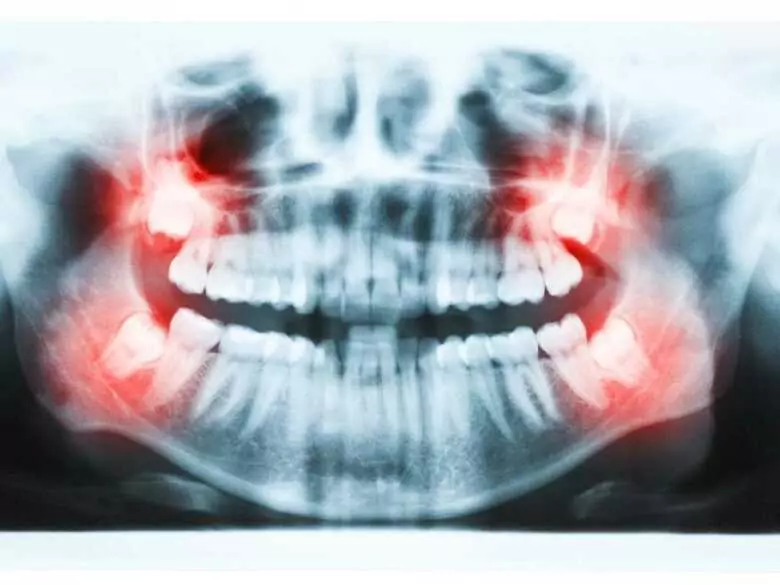

When wisdom teeth come through, it is usually accompanied by pain. The discomfort and unpleasant feeling when the eights come out may subside on their own, but in some cases, active treatment and the intervention of a specialist will be necessary. There are several home remedies that can alleviate the unpleasant feeling and discomfort during the eruption of the eights.